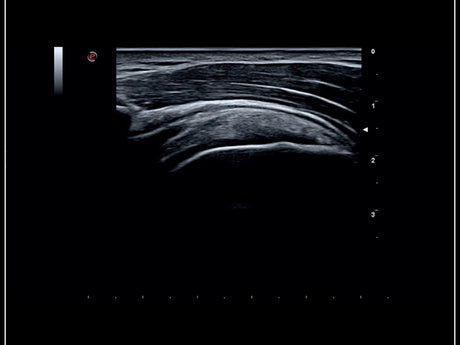

La qualité d’image est au cœur de la philosophie Esaote. Grâce à ses sondes de dernière génération et à son traitement du signal avancé, la marque permet une visualisation fine des structures anatomiques, même les plus profondes. Leurs échographes intègrent des écrans tactiles haute résolution, une interface claire et une connectivité complète, favorisant un flux de travail rapide et efficace.

Les échographes Esaote offrent une restitution d’image d’une grande précision, permettant un diagnostic fiable dans toutes les spécialités. Le traitement numérique optimise le contraste et la netteté, réduisant les artefacts et améliorant la détection des tissus pathologiques. Ces performances sont particulièrement appréciées en gynécologie, où la lisibilité des structures pelviennes ou obstétricales est déterminante.